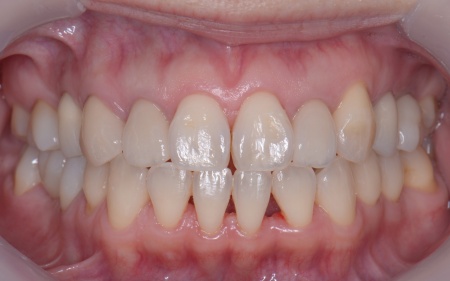

| カウンセリング | 拝見したところ、左下と右上の歯はともに大きな虫歯があり、歯だけでなく被せ物を支える土台の部分にも影響が及んでいました。

さらに、ほかの歯に入っている詰め物や被せ物の周囲にも、過去に治療した部分に再び虫歯ができる二次カリエスが複数見つかりました。 また、噛み合わせを確認したところ、奥歯で噛み合わせた際に上下の前歯が当たらず隙間ができる開咬(かいこう)が認められました。 実際に患者様の場合も、特定の歯に長期間強い力がかかり続けたことで歯や修復物の破損、さらには口腔内全体のトラブルにつながった可能性が高いと考えられました。 修復治療が必要でしたがこの噛み合わせの問題を改善しないまま行うと、治療した歯に再び過度な力が加わって被せ物の破損・脱離や虫歯の再発を招くリスクが高まります。 |

まずは矯正治療を優先し、噛み合わせが整ってから虫歯の再発リスクの低いセラミックの被せ物・詰め物などで歯の形態と機能を回復する方針を提案し、同意いただきました。

矯正治療については、専門的な診断と管理が必要と判断したため専門の矯正歯科医院をご紹介し、他院にて実施していただきました。 矯正治療終了後、改めてお口の中を確認したうえで、歯の状態に合わせ虫歯の除去や土台の修復を丁寧に行い、精密な型取りを実施しています。 最後に噛み合わせ全体のバランスを確認しながら新しく作製した被せ物や詰め物を装着し、見た目に問題がないか、噛み合わせが安定しているかを確認し、治療を終了しました。 |